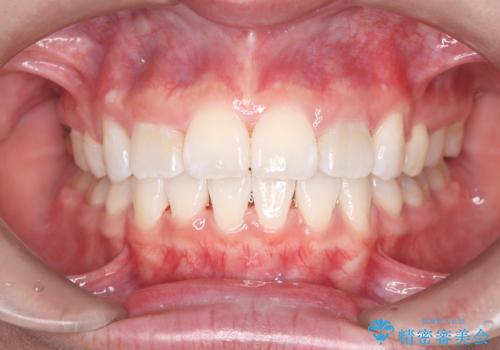

前歯の突出を防ぎながらガタつきを解消。上下左右4番抜歯による審美ワイヤー矯正